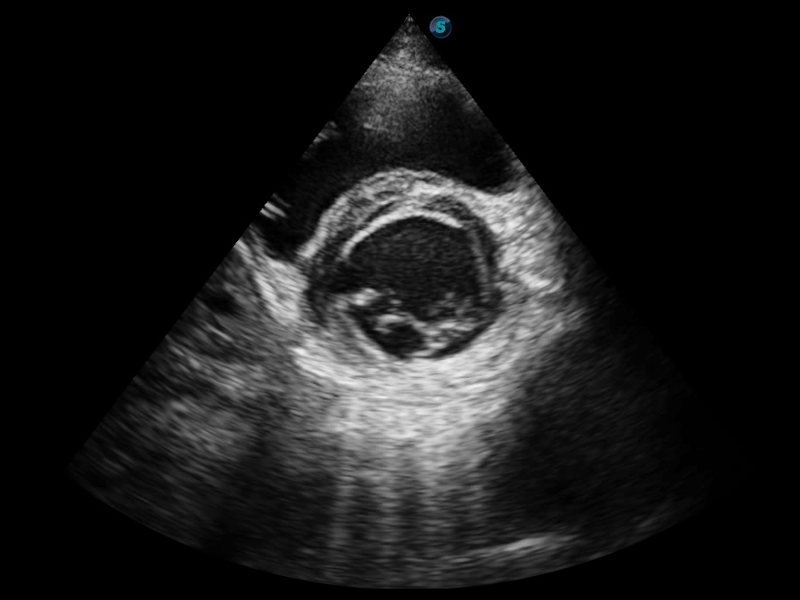

临床图像

S-Fetus 产科扫查助手

S-Fetus基于大数据深度学习算法,能够帮助您在产前筛查过程中智能识别胎儿标准切面、自动测量并录入报告。一个按键,即可智能、精准、高效地获取胎儿生理指标,极大简化您的产科检查操作。